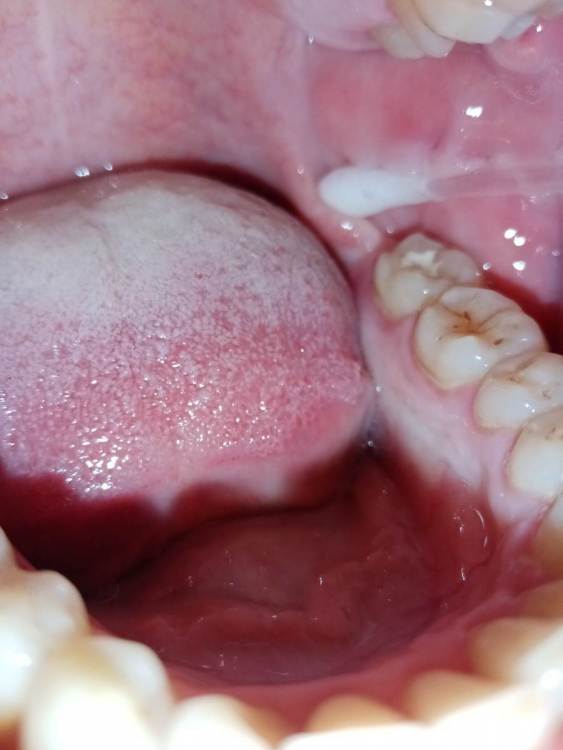

СмирноваД Опубликовано 29 июня, 2023 Поделиться Опубликовано 29 июня, 2023 Уважаемые стоматологи. Прошу Вашей помощи в поиске проблемы. Зуб удалили 2 года назад, но покоя там слизистая не дает. Болит, Разговаривать не дает вообще. Как буд-то там все пришили, и щеку и тяж со стороны горла. Какая-то шишка растет в конце верхней челюсти и как-будто давит там. Срослось оно вот таким образом "V"(со слов врача). Дергает щеку сильно , как-будто она прям пытается оторваться оттуда. и при наклоне головы прям в это место отдает. Со стороны горла тяж пришитый прям лоскутом к челюсти со стороны языка, трется об язык и тянет так сильно, что не дает разговаривать вообще, больно любые напряжения(разговаривать, глотать, пить,смеяться, и т.д.) прям чувствую как оно там все двигается, как нахождении чего-то инородного. Постоянно там все полощу, держу воду, потому что жжёт сильно. И доходит до рвотного рефлекса. Со стороны щеки,за зубом 4.7 корман. Пища попадает , и вытащить ее проблематично. Постоянно ощущение воспаления и лазию туда языком отодвигаю этот тяж, засовываю туда ватный диск, что бы просто снять напряжение и в этот момент могут быть такие жутки спазмы, что замираешь от боли. До трясучки и панических атак уже. Прикусываю там все, при чом даже с шиной (сплинт), щека лезет между зубов, приходится щеку вытаскивать.Шину ношу уже 10 месяцев, а толку нет. Рефлекторно, стараешься не двигать просто правой стороной вообще. Гнатолог , который делал шину, сказал, что нужно убирать рубцы, они все тянут. Но когда дошло дело до хирурга, хирург развел руками и сказал жить так, т.к. он ни чего сделать не может. Мало того у меня проблемы с суставом. а из-за этого напряжения на столько хуже, что к вечеру ни то что бы разговаривать, я и глотать слюну не могу. Сустав у меня теперь болит постоянно от напряжения, жуткие спазмы по всей голове, челюсти, до горла болит, с переходом на шею. При чом все врачи видят эти рубцы, что все прикусываю, трогают и мне больно, но говорят все по разному : один- надо искать, другой - там воспаление, третий- прикус, четвертый -как вы себе представляете это, это нужно было убирать сразу, пятый-сустав. Просто как идти к ортодонту с такими болями? И так же искала врача по пластике, но безрезультатно. На кт и снимках нет ни чего. Помогите, пожалуйста, хоть как-то разобраться. 230310_183333.rar Ссылка на комментарий

СмирноваД Опубликовано 11 августа, 2023 Автор Поделиться Опубликовано 11 августа, 2023 27.07.2023 в 19:43, annda сказал: Нельзя на ортодонтию идти в таком состоянии. Начните с банальной рутинной ежедневной самокоррекции хотя бы-пилатес,йога, Фельденкрайз и прочие подобные штуки. Единственные рубцы,которые у вас есть-это «линия Альба»,,следы прикусывания щек зубами.К месту удаления это не имеет никакого отношения, а к бруксизму -самое прямое. Извинете, Вы, не правы!Линия альбы! Тут ни какого отношения не имеет. Я не могу сфотографировать как выглядет вся слизистая за 4.7. зубом. Ссылка на комментарий

Bier Опубликовано 16 августа, 2023 Поделиться Опубликовано 16 августа, 2023 я вижу рубец на щеке, вы накусали его, ну если он мешает можно его отрезать. Но по источнику боли соглашусь с Анной. Ссылка на комментарий